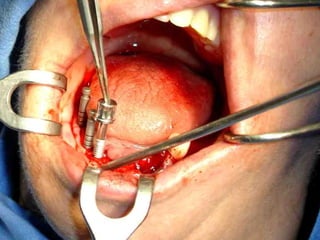

Reimplante ortodóncico

Receptor

Receptor momento de trasplante

Trasplante 3 meses de evolución